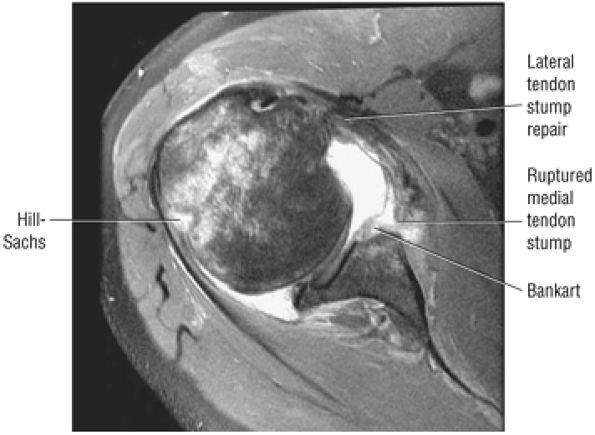

cystic change in the posterior greater tuberosity subjacent to the rotator cuff tear (Fig. 8.55G).

-

Interstitial tear extending from the posterior supraspinatus tendon to the anterior infraspinatus tendon. The anterior margin of the tear extends to the articular surface.

Type 2 SLAP tear extending primarily into the posterior superior labrum

Anterior inferior acromial spurring, os acromiale, and mild subacromial/subdeltoid bursitis